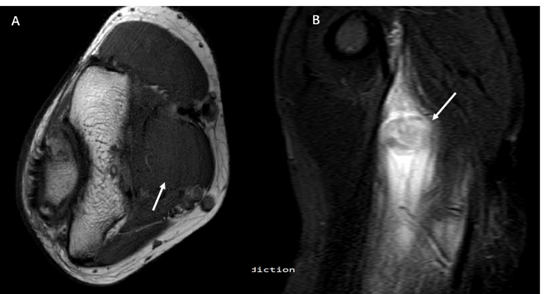

A low-attenuation soft-tissue mass with associated calcifications, typically the peripheral rim becomes increasingly calcified and the central lucent zone is isodense to adjacent brachial muscles. AP view CT showed “popcorn” calcification in soft tissue with radiolucent center and sagittal plane CT revealed the “popcorn” calcification is not from adjacent bones. The axial view CT demonstrated clearly that the calcification mass anterior to distal humerus in brachial muscles (Figure 4). The MRI appearance follows the isointense to hypointense to skeletal muscle on T1-weighted sequences. T2-weighted sequences will appear hyperintense to surrounding muscles. The peripheral low signal intensity can be seen (Figure 5).

Figure 5: The MRI appearance that follows the isointense to hypo intense to skeletal muscle on T1-weighted sequences (An arrow in A). T2-weighted sequences will appear hyperintense to surrounding muscle. The peripheral low signal intensity can be seen (An arrow in B).